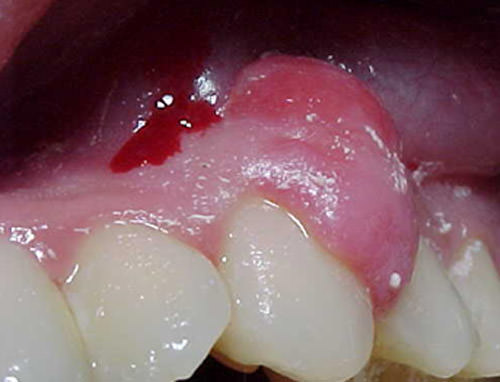

Al examen clínico se observó que la encía vestibular superior presentaba un aspecto ligeramente edematoso con una masa voluminosa localizada entre 23 y 24, de superficie lisa, con cambios de coloración hacia apical de la lesión, hacia la zona incisal de la misma el color es igual a la encía circunvecina, de consistencia firme, base sésil de 10mm en sentido apical-incisal y de 6mm en sentido distal-mesial, indolora (Fig.1). La encía por palatino presenta un aspecto aparentemente sano. La encía vestibular inferior y la encía lingual presentan un aspecto moderadamente edematoso, localizado en la zona antero inferior. Al sondaje periodontal la profundidad osciló entre 1 y 2mm, excepto entre 23 y 24 donde el sondaje fue de 5mm debido a que la papila llegaba hasta el punto de contacto. Se presentó leve sangrado en esta zona y en la zona antero inferior. Pocos irritantes locales tipo cálculo dental localizado en la zona antero inferior. Índice de O´Leary (mide la cantidad de depósitos teñidos de placa acumulada en las superficies libres dentales utilizando soluciones reveladoras como la fuccina) de 15%. No se detectó movilidad dental. Radiográficamente no se observaron cambios en la cortical ósea, nivel óseo y trabeculado óseo.

Fig 1

Características clínicas: masa voluminosa localizada entre 23 y 24, de superficie lisa, con cambios de coloración hacia apical de la lesión; consistencia firme y base sésil. De 10mm en sentido apico-incisal y de 6mm en sentido mesio-distal, indolora